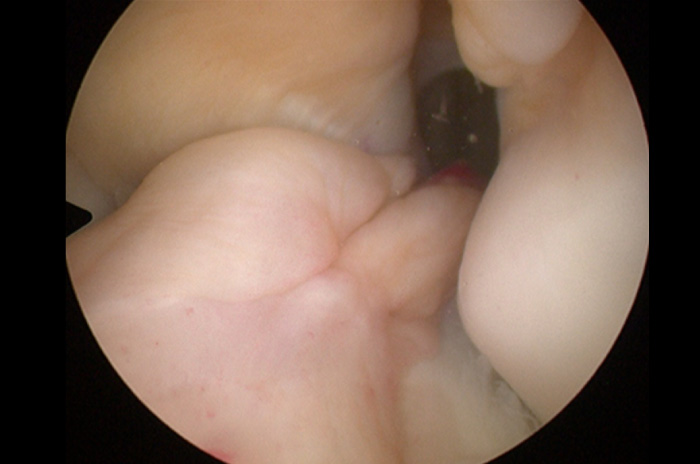

Con guías y brocas especiales se perforan túneles en la tibia y en el fémur, el injerto, es decir, el nuevo ligamento se coloca a través de estos túneles. La fijación de este nuevo ligamento se lleva al cabo con dispositivos especiales como el ACL TightRope® o el Endobutton® en el femur y en la tibia habitualmente con tornillos interferenciales (absorbibles, biocompuestos o metálicos).